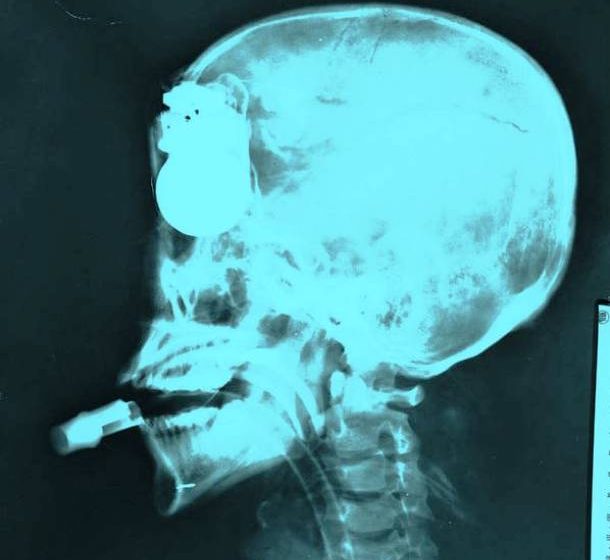

1. X-Ray of a Suicide Bomber *All images sourced from Reddit* This is a hand…